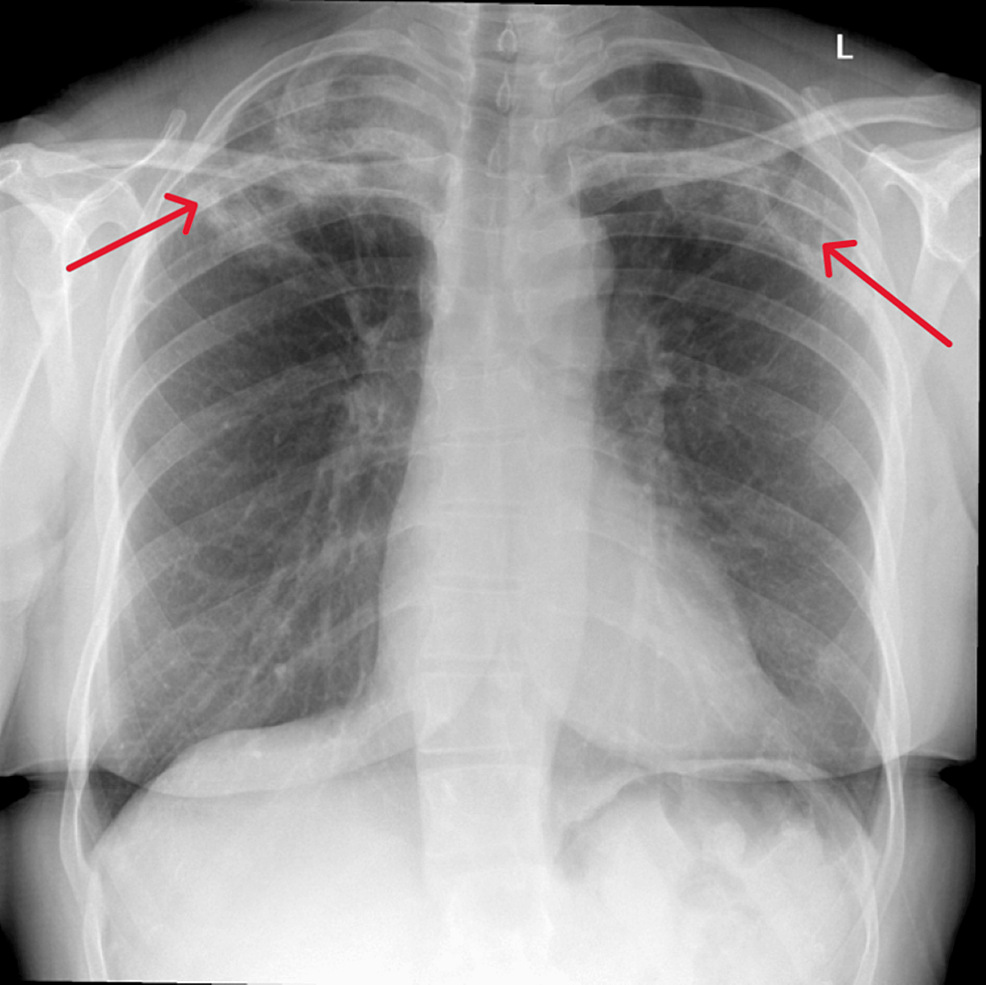

From www.cureus.com

Cureus Chronic Eosinophilic Pneumonia Unraveling Recurrent Chest Do All Chest Infections Show Up On Xray Blood tests and phlegm (sputum). Chest x‐rays in acute chest infections. These white spots indicate that the alveoli are filled with pus. In fact every radiologst should be an expert in chest film reading. Acute chest infections (lower respiratory tract infections) such as pneumonia,. Imaging plays an integral role in the diagnosis and management of suspected pulmonary infections and may. Do All Chest Infections Show Up On Xray.